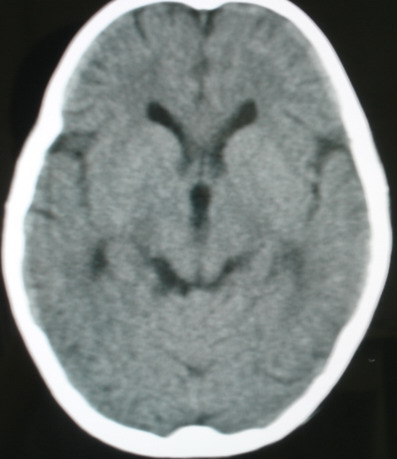

标题: PED0834:M8Y,考虑右侧海绵窦血管瘤 [打印本页]

标题: PED0834:M8Y,考虑右侧海绵窦血管瘤

m/8y,右侧眼睑下垂数天,头昏,无呕吐、无外伤史。无搏动性突眼。病人明天来增强。

不除外右侧海绵窦脑膜瘤,建议增强进一步检查。